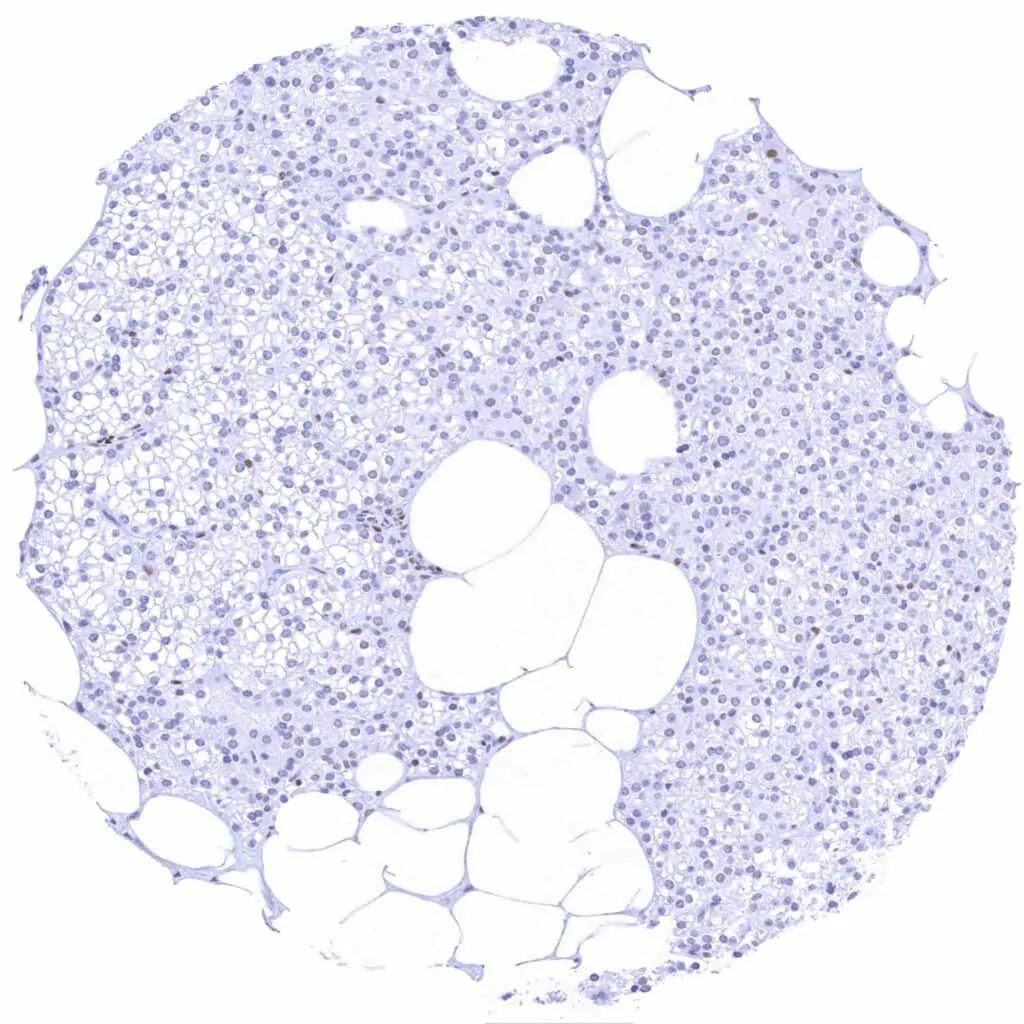

Bone marrow – Weak to strong TLE1 positivity of a significant fraction of cells-1